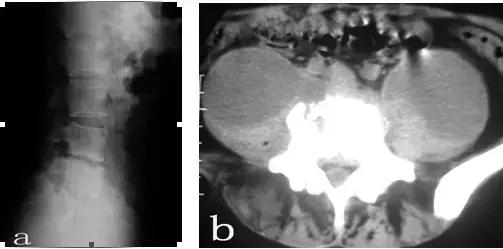

患者郭某,女性,25岁。因腰痛一年余,曾经在多家医院就诊,诊断为腰椎间盘突出,给予对症治疗,当时有所减轻,近来腰痛加重,经检查后考虑腰椎结核而到我院就诊。查体:脊柱向右侧弯曲,L4-5棘间压痛,叩击痛。左侧腹股沟区可触及100px×125px包块,触之波动感。实验室检查:血清抗结核阳性,血沉69mm/h,C-反应蛋白164.9mg/dl,PPD试验强阳性。腰椎平片(图a)示:腰4/5间隙变窄,L4椎体上缘骨质破坏。腰椎CT(图b)示:L4、L5椎体骨质有破坏,并有死骨形成,双侧腰大肌内可见液性暗区。腰椎MRI(图c)示:椎间盘等T1略短T2信号,临近骨组织呈长T1长T2信号,正常椎间盘信号消失,L4椎体下半部分L5上半部分骨质破坏,周围软组织肿胀,腰椎双侧腰大肌及骶前脓肿形成。入院诊断:腰椎结核(L4/5),腰大肌脓肿(双侧),骶前脓肿。入院后给予H.R.Z.E初治方案,同时在CT引导下行双侧腰大肌脓肿穿刺置管引流术(图d),引流后病人症状明显缓解,血沉(36mm/h)、C-反应蛋白(97.9mg/dl)明显下降,复查腰椎CT(图e)脓肿明显减少,经过抗结核治疗四周后给予行后路椎弓根钉棒系统内固定、前路病灶清除取髂骨植骨融合术(图f、g)。

腰椎X检查(图a)可见生理前凸减小、椎间隙变窄,相应椎体上下缘骨质疏松。

CT检查(图b、e)可见椎体破坏、死骨、椎旁脓肿、腰大肌脓肿及椎管内的变化等。